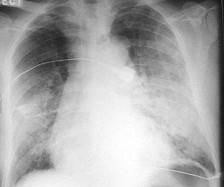

问题 男,67岁,近1个月出现活动后心悸、气短,双肺底可闻及湿性啰音,腹部检查肝脾肋下未触及,双下肢明显凹陷性水肿。胸部X线检查如图所示,超声心动图左室舒张末径61mm,左室射血分 数39%。 该患者处于 ( )

选项 A、慢性心力衰竭失代偿阶段 B、无心力衰竭 C、急性心力衰竭失代偿阶段 D、慢性心力衰竭代偿阶段 E、急性心力衰竭代偿阶段

答案 A